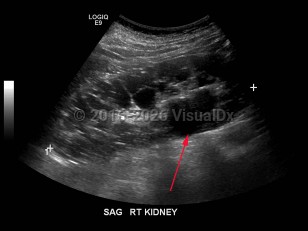

Imaging Studies image of Polycystic kidney disease - imageId=7911488. Click to open in gallery.  caption: '<span>Grayscale ultrasound image demonstrates enlarged right kidney with multiple cysts, some simple and others complex. The left kidney had a similar appearance.</span>'

Grayscale ultrasound image demonstrates enlarged right kidney with multiple cysts, some simple and others complex. The left kidney had a similar appearance.